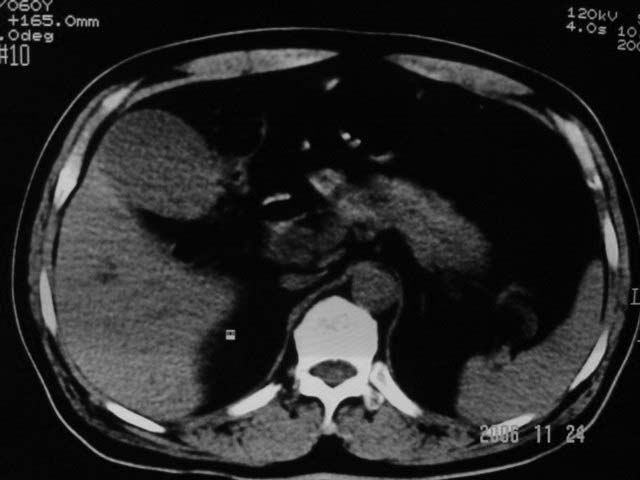

标题: CT5395:男、60岁,皮肤、巩膜黄染伴上腹部疼痛20天 [打印本页]

标题: CT5395:男、60岁,皮肤、巩膜黄染伴上腹部疼痛20天

支持楼主:1、胆总管结石; 2、胆囊增大,胆囊炎?

感觉不是结石可能,与上一层面联系应该是门脉区影像,图像显示不佳,胆总管显示不清[特别是胰头以上段],目前影像只能说肝内外胆管扩张,胰管扩张,胆囊扩大。提示胆总管远端梗阻。可考虑肿瘤或结石所致

胆总管内结节状高密度灶,边缘隐约可见低密度环绕,首先考虑结石伴肝内胆管扩张; 2、胆囊增大,胆囊炎

不过最好与超声结合或增强扫描